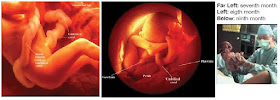

胎兒的成長

第1個月 受精卵長成尚未具人形的小胚囊。

(註:Blastocyst有人翻譯為胚囊;有人翻譯為囊胚或胚胞。)

第2個月 已稍具有人形,開始發展基本器官,心臟也開始跳動。

第3個月 更具有人形,內臟透明可見。

第4個月 內臟型態幾乎長成。

第5個月 消化系統開始運作,長出胎毛。

第6個月 胎兒各種器官大致發育完成,開始有感官知覺。

第7個月 腦部逐漸發育完全,眼睛可以睜開。

第8個月 骨骼、肌肉、神經系統逐漸發育完成。

第9個月 胎兒的身體器官與組織已發育完成。

胎兒成長的大略過程(有些圖沒有照實際的比例表示):

圖03. 有些專家將胚胎發育的九個月分成三期(First、 Second、

Third Trimesters),詳細之區分過程,有興趣的網友請參考圖03。

圖10. 三個月的胎兒。生命進入第三個月(9—12週)時,稱為胎兒。第八週胚的頭部佔整個胚全長的l/2,以後頭部的比例減小。至第十二週末身體重量增加約1倍。內臟系統已開始具有功能,能吞嚥羊水,變成尿液排泄出來。

圖11. 第四個月(13—16週),胎兒身長已達16公分(cm),體重約140公克,生長迅速。胎頭與身體的比例不再是1/2:1/2那麼與成體不同了,腿相對變長,骨骼迅速骨化,已能進行反射動作。在肝、胃、腸的發揮功能作用下,已可形成綠色的胎便,等出生後才會排出體外;心跳率是成人的兩倍。

圖13. 第五個月(17—20週),孕婦就會感覺腹內胎兒在踢自己的胎動。可以在腹部聽到胎心音,一般為120—160次/分。胎兒已具備聽力,能聽見聲音,可開始進行胎教。男胎兒外生殖器官(例如陰莖penis等)已經發育完全。此時胎兒體長約25公分,體重約400公克。

圖14. 第六個月(21—24週),胎兒約35公分(cm)長,約900公克重,皮膚出現胎毛(lanugo)。指甲和趾甲出現,會打嗝、會吮自己的拇指,體表有一層白色的脂肪(vernix),兩條胳膊彎曲在胸前,兩隻膝蓋提到腹部,看起來像個小老頭兒。這時早產兒如無人工呼吸器輔助,往往僅能存活幾個小時,因為6個月時,一般呼吸系統尚未完全發育。

圖15. 第七個月(25—28週),胎兒約40公分長,1400公克重,這時出生雖能自行呼吸,但表面張力素(surfactant)仍未分泌出來,以降低肺泡的表面張力,如無人工呼吸器的輔助,胎兒存活的機率仍不太高。

第8個月 骨骼、肌肉、神經系統逐漸發育完成

圖16. 八個月(29—32週),胎兒身長約43公分,體重約2200公克。胎兒在子宮內活動自由,胎動協調,位置基本固定,一般頭部朝下。神經系統進一步完善,肺及其它內臟已發育完成。這時出生的早產兒,如在保溫箱裡精心照料,一般已能存活。

第9個月 胎兒的身體器官與組織已發育完成。

第九個月(33—36週),胎兒約53公分長,體重在4週內可以增加1000公克達到3200公克,發育基本完成。這時出生的早產兒如果能精心照顧,存活率可達90%以上。

第十個月(37—40週),胎兒完成發育,皮膚微帶粉紅色,胸部發育良好,男性睾丸常位於陰囊內。